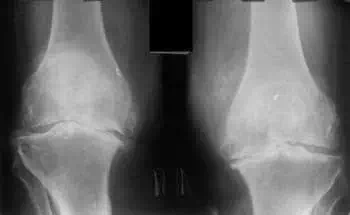

Acum 2 ani, m-am confruntat pentru prima dată cu dureri ușoare în genunchi și șold. Durerea nu a fost puternică, nu i-am acordat prea multă atenție... După cum s-a dovedit, bolile articulare sunt foarte grave și trebuie tratate imediat, nu amânate cum făceam eu! Într-o zi foarte obișnuită, am simțit o durere nu foarte puternică, dar ascuțită în genunchi, iar articulația șoldului a început să doară serios, am crezut că nu este nimic strașnic, va dispărea ca de obicei. Am cumpărat medicamente și am început să le aplic. Am îndurat timp de aproximativ 1 săptămână, starea mea a început să se înrăutățească brusc, durerea a devenit insuportabilă, durerea acută a început în articulația șoldului, am decis să merg la medic pentru prima dată. Mi-au făcut un diagnostic ieftin, iar medicul meu s-a uitat la rezultatele examinării și a spus:

"De ce mai înainte ați ignorat simptomele? Aveți artroză! Artroza, dacă doriți să nu deveniți invalid, trebuie îndăpărtată cu o intervenție chirurgicală pe șold și genunchi!”

img img

Am fost șocată!! Am început să intru în panică, nu aveam bani pentru operație și nu eram deloc pregătită pentru un astfel de scenariu! Suma operațiunii a fost cosmică... și nu eram deloc sigură că voi suferi o astfel de operație la bătrânețe. Am decis să refuz, i-am cerut să-mi prescrie medicamente pentru tratament.

img

Înlocuirea articulației este foarte costisitoare și o operație foarte gravă.